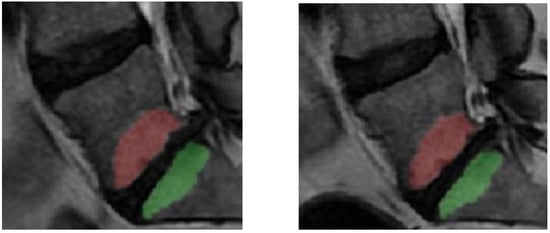

Figure 2. Example of segmented Modic change (MC) in L5 and in S1 at MRI without (left) and with (right) spinal loading.